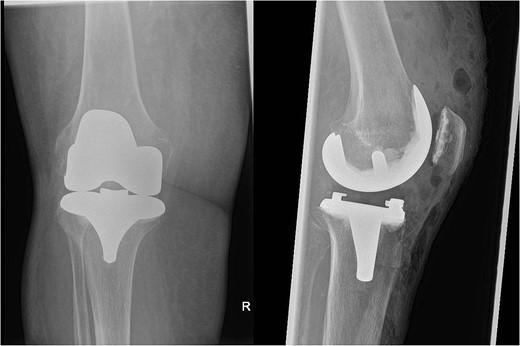

In July 2023, a 75-year-old female patient underwent elective right total knee replacement with patellar resurfacing for osteoarthritis (Fig. 1). Prior to this procedure she was able to mobilize using a walker. Her comorbidities included hypertension, type 2 diabetes mellitus, diverticulosis, Parkinson’s disease, and a body mass index of 33.2. Surgery was uneventful so she was discharged home and requested to continue with rehabilitation (Fig. 2). Two weeks postoperatively she noticed redness and warmth surrounding the knee joint and a further 2 weeks later she felt a “pop” whilst walking. She then presented with a painful, swollen right knee on which she was unable to weight bear. X-rays identified a closed right patellar sleeve fracture. It was assumed that the pain and inflammation was due to the fracture and not due to infection and the decision was taken to treat the fracture non-operatively. The knee was splinted, and she was allowed to touch weight bear with a frame.